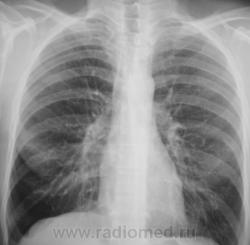

Контроль через 1 месяц после противовоспалительной терапии.